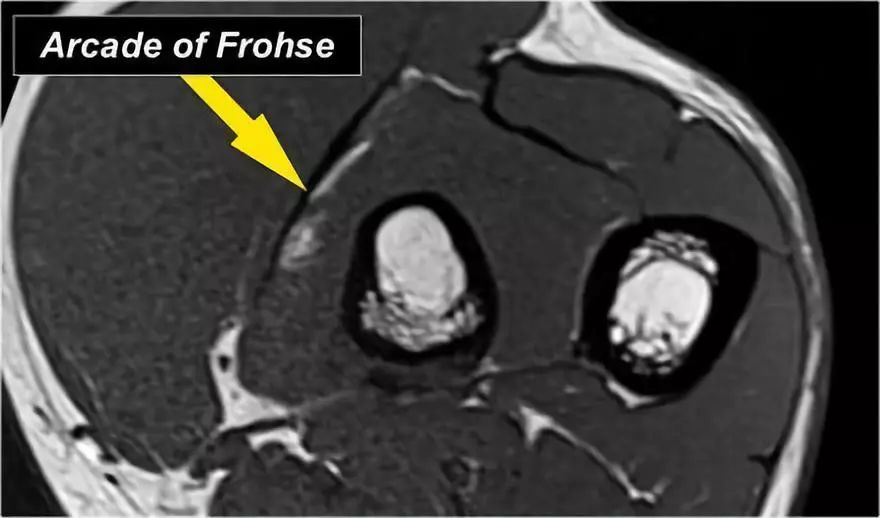

深分支形成后骨间神经,穿过Frohse拱门(箭头)的旋后肌。